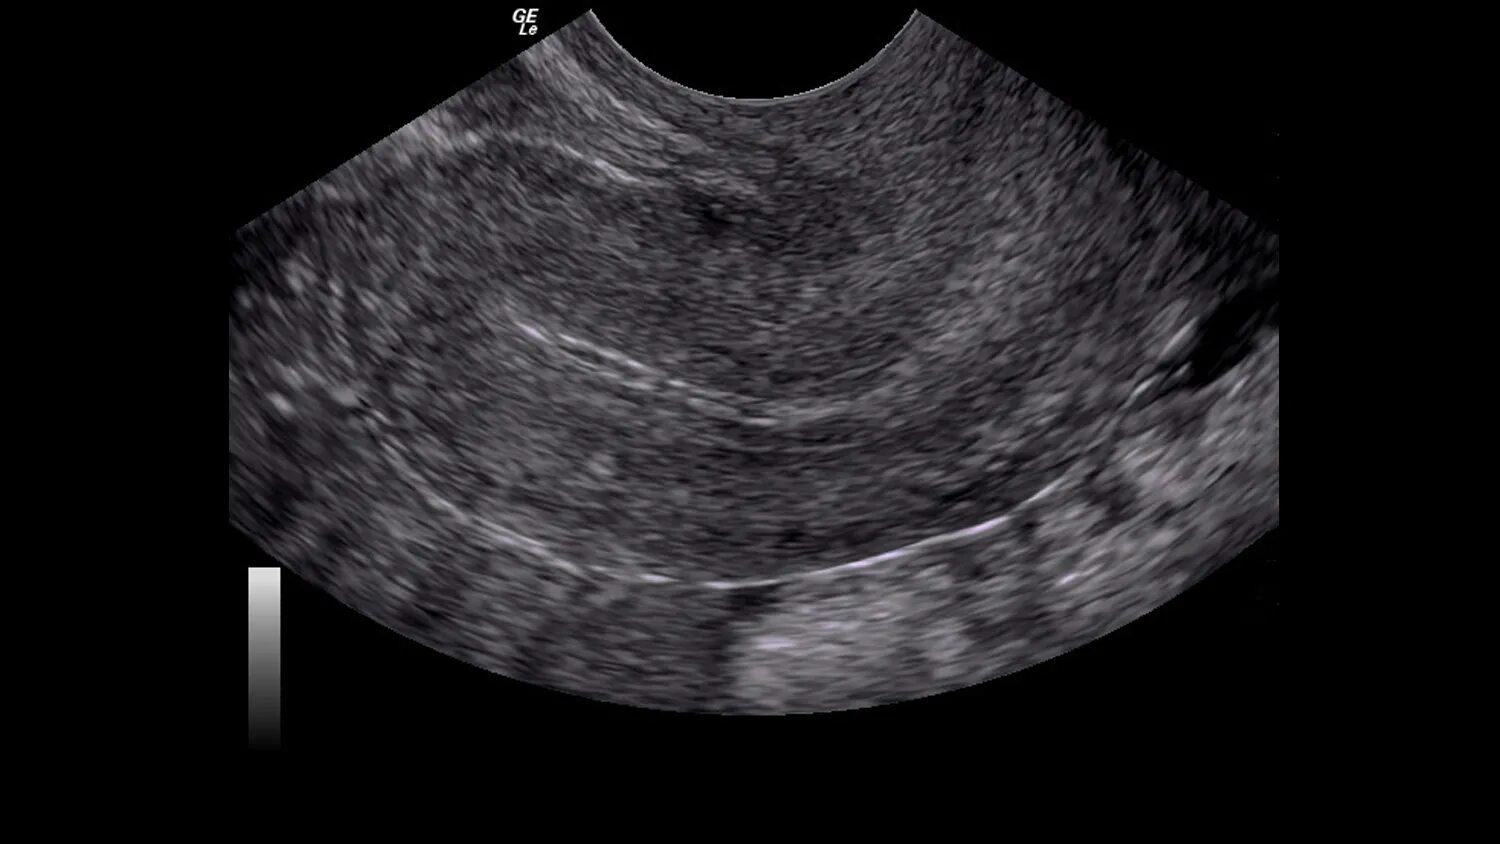

Серозометры в матке что это такое